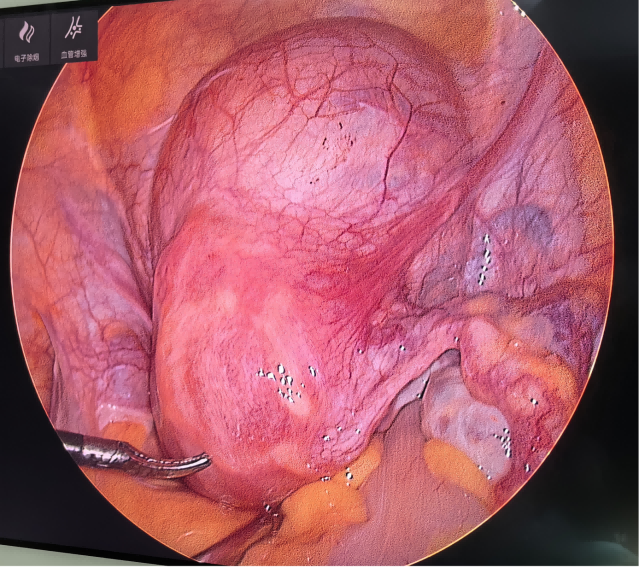

图2 腹腔镜镜下的子宫及子宫肌瘤

近日,中山市神湾医院妇产科成功为一位因巨大子宫肌瘤导致月经过多,严重贫血的患者实施了腹腔镜下子宫肌瘤剔除术。

该女性患者34岁,近期月经量过多,来院检查发现子宫肌瘤大小约11cm,血红蛋白最低降至62g/L(正常女性≥110g/L),并出现乏力、头晕,活动后心慌等贫血症状。

经团队评估,最终通过微创手术精准剔除肌瘤,术后恢复良好,贫血问题得到显著改善。